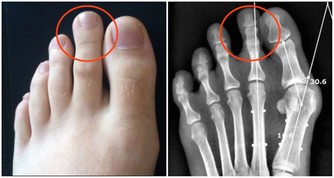

增進食慾,維持神經正常活動,預防腳氣病、神經性皮炎等。